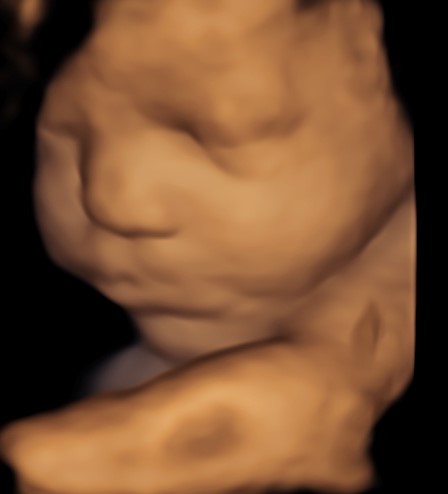

4D/5D/HD Ultrasound Gallery

Gallery